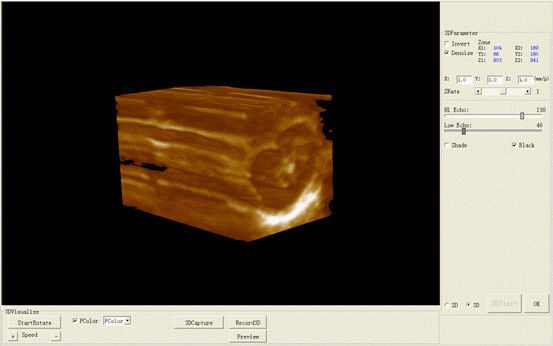

Permanent Storage: 1024: Abdomen (Distance, circumference, area, volume)